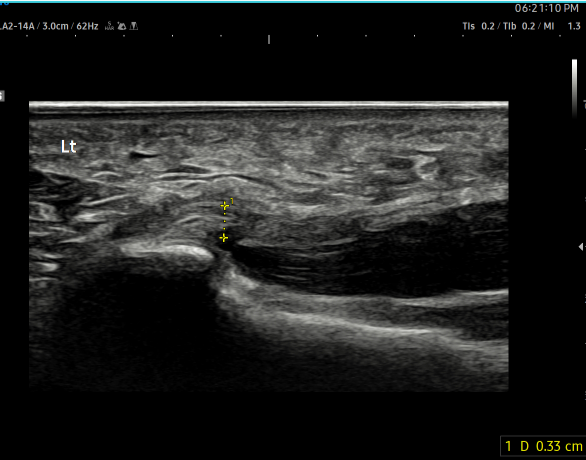

- 치료기간 : 25 .6 .19 ~ 25 . 10 . 23

- 치료횟수 : 15 회 (아피톡신+극초단파)

치료 전 (족저근막 두께 0.44~0.61cm)

치료 후 (족저근막 두께 0.33~0.36cm)